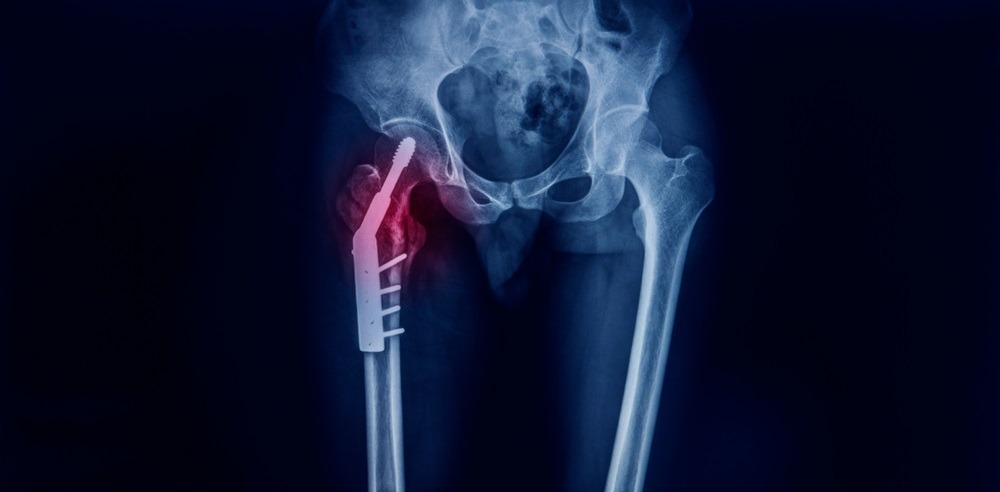

Η ολική αρθροπλαστική ισχίου ή γόνατος είναι η πιο αποτελεσματική χειρουργική επιλογή για την αποκατάσταση της άρθρωσης σε προχωρημένα στάδια αρθρίτιδας. Η σύγχρονη τεχνολογία, όπως η ρομποτικά υποβοηθούμενη χειρουργική, επιτρέπει μεγαλύτερη ακρίβεια, μικρότερη επιβάρυνση των ιστών και ταχύτερη ανάρρωση.

Η επέμβαση αντικαθιστά την κατεστραμμένη άρθρωση με ένα τεχνητό εμφύτευμα, επαναφέροντας την κινητικότητα και εξαλείφοντας τον πόνο. Ο στόχος δεν είναι απλώς η αντιμετώπιση των συμπτωμάτων, αλλά η επαναφορά της ελευθερίας κινήσεων και της ποιότητας ζωής που χάθηκε λόγω της αρθρίτιδας.